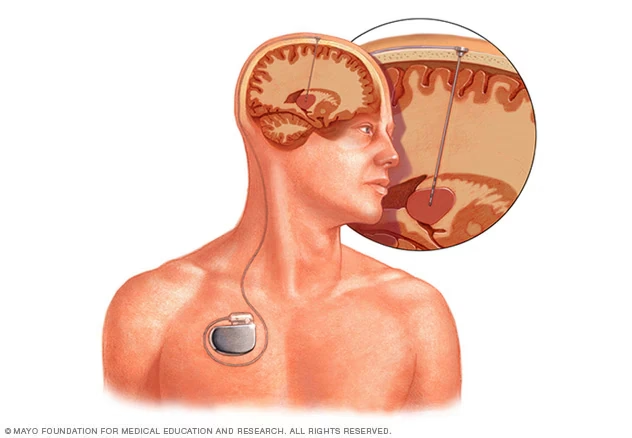

La ECP implica la implantación de electrodos finos en áreas específicas del cerebro que controlan el movimiento o el estado de ánimo. Estos electrodos están conectados a un dispositivo similar a un marcapasos, llamado neuroestimulador, que se implanta debajo de la piel, generalmente cerca de la clavícula. Este dispositivo envía pulsos eléctricos continuos a las regiones cerebrales objetivo, ayudando a modular la actividad neuronal desorganizada que causa los síntomas.

El proceso comienza con la determinación precisa de la ubicación óptima para la colocación de los electrodos (llamados 'leads'). Neurocirujanos experimentados implantan uno o más de estos leads dentro de estructuras cerebrales específicas. Estos leads se conectan a través de un cable aislado de extensión a un pequeño neuroestimulador que, como se mencionó, se coloca quirúrgicamente bajo la piel, usualmente en la parte superior del pecho.

La implantación del neuroestimulador se realiza generalmente bajo anestesia general. Se crea un 'bolsillo' bajo la piel, usualmente debajo de la clavícula o en el pecho/abdomen, y se coloca el dispositivo. El cable de extensión del lead cerebral se conecta al neuroestimulador. Las incisiones se cierran con suturas o adhesivos.